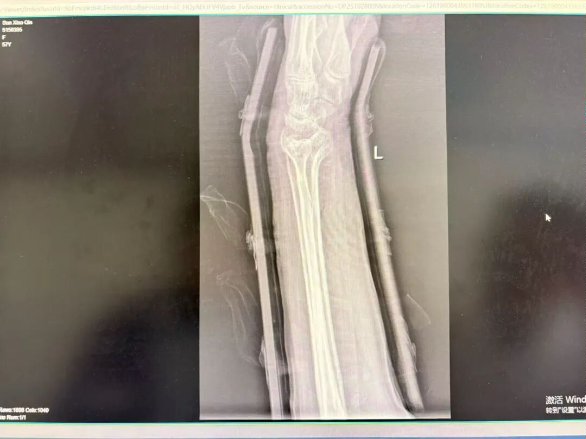

(石膏X光图示)

(夹板X光图示)

我们的最终选择,源于对您X光片的精确判读、对您骨折稳定性的评估,以及对您个人情况和康复期望的综合考量。我们的目标都是一致的:让您的骨头愈合,更要让您的手臂重返灵活,未来能轻松地工作,再次愉快地和生活比个“耶”。